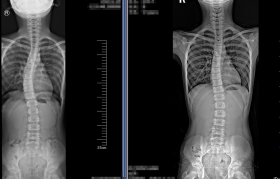

2. 度数迷思的破除 20度以下:通过瑜伽、游泳等对称性运动可完全矫正...